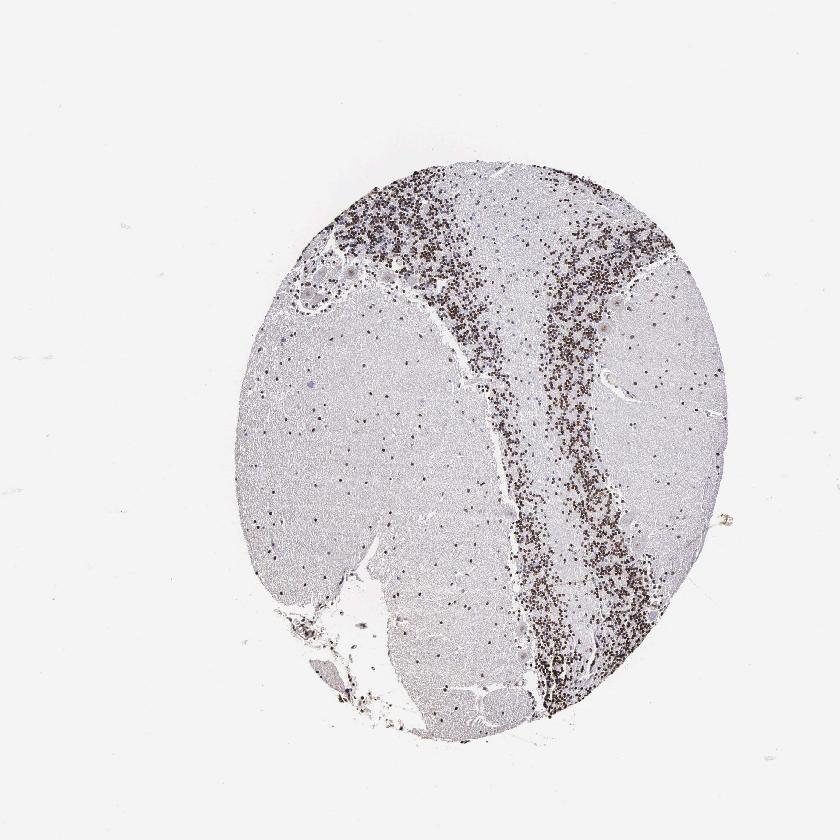

BRAIN CEREBELLUM Show tissue menu

CEREBELLUM - Expression summary

CEREBELLUM - Antibody stainingi

Antibody staining in the annotated cell types in the current human tissue is reported as not detected, low, medium, or high, based on conventional immunohistochemistry profiling in selected tissues. This score is based on the combination of the staining intensity and fraction of stained cells.

Each image is clickable and will lead to virtual microscopy that enables deeper exploration of all samples and also displays staining intensity scores, fraction scores and subcellular localization as well as patient and tissue information for each sample.

Antibody HPA000637

Purkinje cells Low

Cells in granular layer Low

Cells in molecular layer Medium